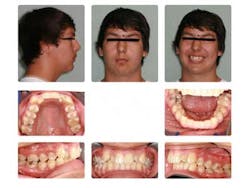

Case report A healthy 16-year-old male presents with Class II bite, an obtuse nasolabial angle, a slight, long concave profile with deficiency in the growth of the mandible, and inadequate spacing for the maxillary teeth. What are the options and talking points for this treatment plan?1. There is likely very little growth potential left in this patient, so trying to capture any remaining growth would be minimal.

2. If we were to focus only on the occlusion (minus profile, etc.), then it would be simple to extract the maxillary 4’s (1st bicuspids) and then acquire a somewhat ideal alignment of the arches.

3. In reference to point No. 2, orthodontic treatment planned without mandibular jaw advancement surgery in these types of cases generally will build in more dental compensations for skeletal variation (2), as the profile is compromised even more with a wider nasolabial angle, longer profile, and thus limiting the ability for any future facial profile correction.

4. The ideal treatment and recommendation would be to perform a lower jaw advancement surgery to give an ideal position of skeletal and dental components. Worms et al. reported that the total interrelationships of surgical and orthodontic contributions are in the best care and interest of the patient long term. (2)

5. It can be argued that mandibular jaw advancement surgery could, down the road, cause TMJ concerns/issues or create a dual bite. A study done by Mihalik et al. reported that orthodontics-only patients reported fewer functional or TMJ problems than did the surgery patients, but patients who had their mandibles advanced were significantly more positive about their dentofacial images. (1) This is an important concept to remember — beauty is in the eye of the beholder!

6. If surgery is not an option or desired at that time, then many would consider again not to extract the upper 4’s and use a functional appliance, such as a Herbst to attempt to advance the mandible while aligning the teeth as best as possible. In the end, however, there would likely be excess overjet of the anterior teeth in this type of compromise.

It could be concluded with the aforementioned talking points that there is not a right or wrong way to proceed in cases like this. Some options are better than others, but this is the take-home point: If a Class II patient (as presented herein) does have the upper 4’s removed, it exacerbates the existing profile and limits virtually any potential for a correction of profile in the future. It is, therefore, vital to discuss all risks, benefits, complications, and alternatives so the patient can make the best decision possible. Assuming no regard to cost or possible complications, the mandibular advancement would be considered by most to be the preferential treatment in this case, as it resolves the core problem — mandibular deficiency. In this case, the patient was not willing to undergo a surgical procedure at this time, so the treating orthodontist advised the family against the removal of maxillary teeth in order to preserve facial profile and allow for possible future mandibular advancement procedure.